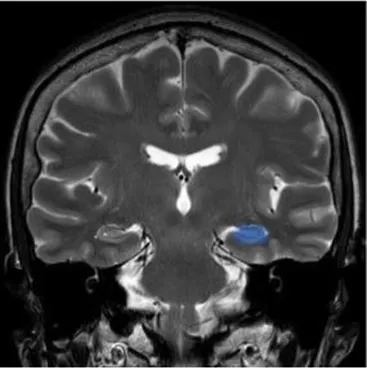

Studying the SNDG with conventional MRI, disruption to global functional connectivity has been revealed in the ipsi-lesional corticospinal tract and in the inter-hemispheric connections (corpus callosum), in the bilateral inferior fronto-occipital fasciculus and in the bilateral superior longitudinal fasciculus (34–36), in the ipsilateral thalamus, in the substantia nigra, hippocampus and in amygdala (37–39).

The involvement of these areas distal to the primary lesion defines the onset of cognitive and behavioral symptoms different from those primarily related to stroke area (36, 40). For example, involvement of the thalamus can lead to hyperalgesia; damage in the substantia nigra provokes Parkinson-like symptoms (slow movements, tremor, stiffness and difficulty with walking and balance); involvement of amygdala results in difficulty with memory processing and emotional reactions, whereas an involvement of hippocampus to memory impairment (Table 1).